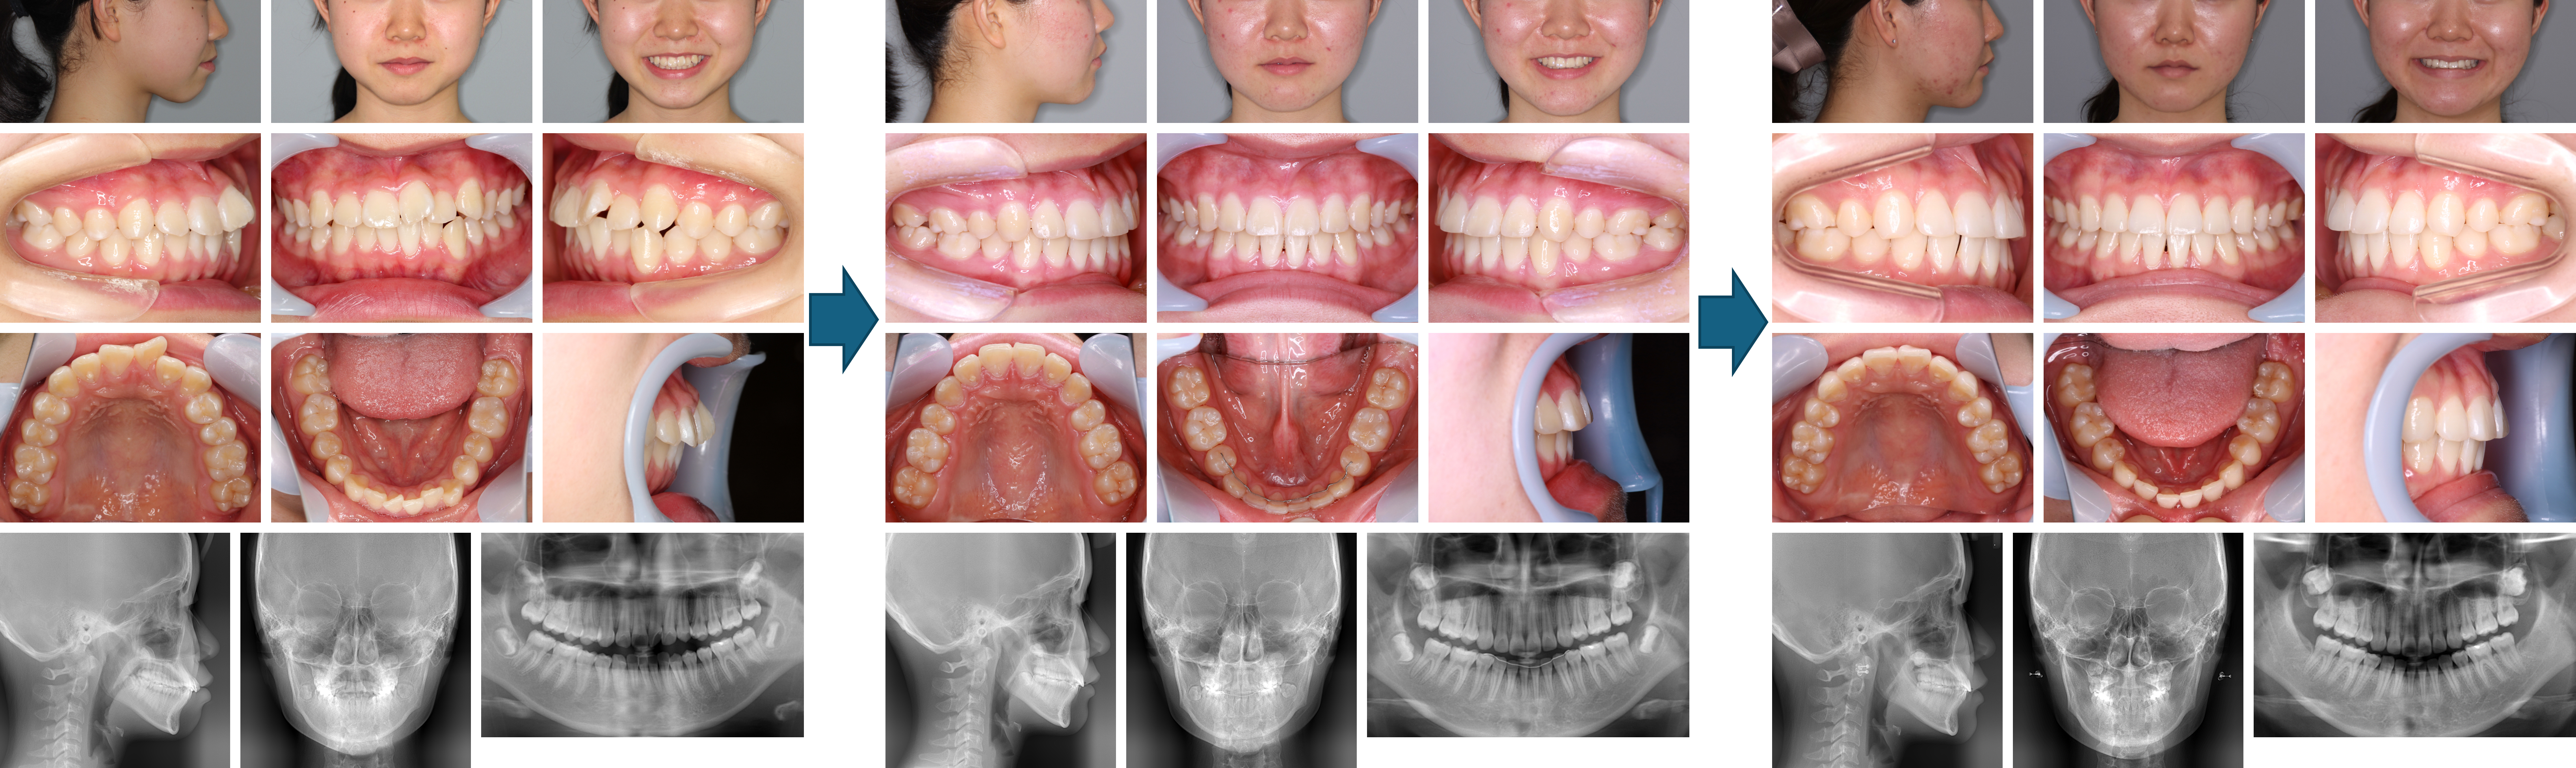

【治療例】初診時年齢:15歳2か月 / 性別:男性 / 主訴:上の前歯が出ている

症例の概要:上顎前歯の唇側傾斜によって口唇閉鎖時は上唇の突出とオトガイの過緊張が認められました。最初に上顎の抜歯を行い、下顎の抜歯は治療経過から考慮することを患者さんにお伝えして治療を開始しました。結果、下顎は一部の歯の隣接面を削ったが抜歯をせずに顔貌の改善および緊密な咬合を獲得することができました。

主訴:上の前歯が出ている

診断名: 著しく上顎前歯が唇側傾斜した下顎後退型の骨格性Ⅱ級、ローアングル症例

使用した主な装置: マルチブラケット装置(金属)、サービカルヘッドギア、顎間ゴム

抜歯/非抜歯および抜歯部位: 右上4番8番、左上4番、右下8番の抜歯

治療期間:2年9か月

治療回数:38回

リスクの副作用:歯の移動、装置による口内炎、抜歯などの痛みや歯肉退縮、歯根吸収、後戻りなどの可能性がある